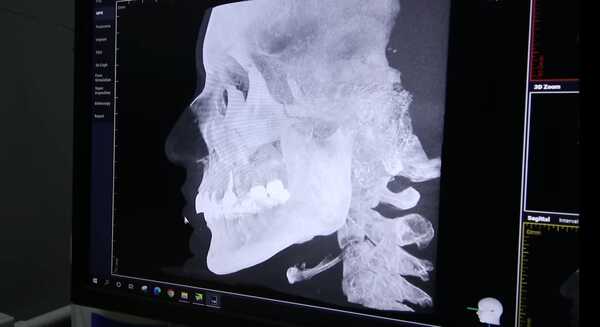

ล่าสุด 17 มกราคม 2566 ใหม่ ดาวิกา ได้เผยในคลิป Davikah Channel ที่จะทำคอนเทนต์พลีชีพ เผยทุกความลับของการศัลยกรรม ว่าไปทำจมูก ทำหน้า ทุบโหนกแก้มที่ไหน งานนี้ใหม่ได้ไปสแกนใบหน้าที่โรงพยาบาลด้วยเครื่อง CT Scan และเห็นใบหน้าได้เลย 360 องศา จะเห็นทั้งซิลิโคน ฟิลเลอร์ ถ้าเคยทำอะไรมาจะรู้หมดเลย

โดยในตอนแรก ใหม่ ดาวิกา ให้ทีมงานที่เคยทำศัลยกรรมมาลองดูสแกนทดสอบเครื่องก่อน และผลปรากฏว่าเจอซิลิโคนที่จมูก หน้าผาก จากนั้นถึงคราวที่ใหม่ ดาวิกา เป็นคนสแกนบ้าง ซึ่งพอสแกนเสร็จก็ถึงกับมือเปียก เหงื่อแตก แต่ใหม่ดาวิกาก็บอกว่า จะได้ไขข้อครหาคนในอินเทอร์เน็ต ที่บอกว่าพาใหม่ไปทำหน้ามา หรือพูดเอาเองว่าใหม่ทำหน้า

ซึ่งพอผลออกมาปรากฏว่า ใหม่ไม่ได้ทำหน้าเลย จมูกไม่มีซิลิโคน คางก็ไม่อะไรทั้งนั้น สิ่งที่เห็นชัด ๆ คือ รากฟันเทียม !ส่วนที่บอกว่าทำตาหรือเปล่า คุณหมอก็มาช่วยคอนเฟิร์มว่า อย่างของพี่เกล้าคือทำตามา ส่วนของใหม่ ดาวิกา คุณหมอบอกว่าเนียนมาก ดูไม่รู้ ซึ่งให้ฟันธงเลยคือ ใหม่ไม่ได้ทำตา